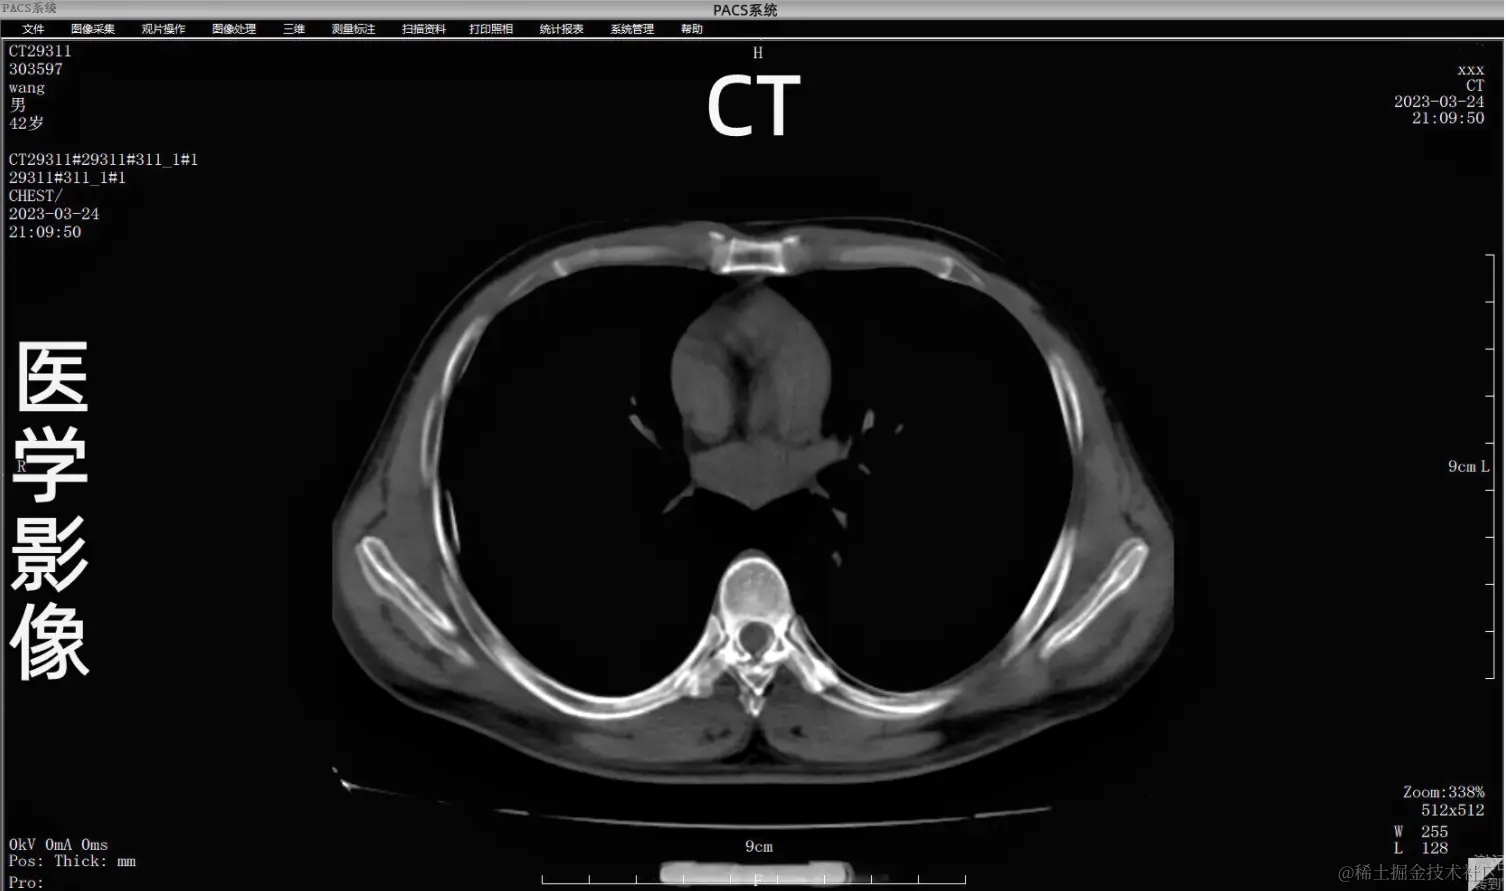

PACS连接DICOM接口的医疗器械(如CT、MRI、CR、DR、DSA、各种窥镜成像系统设备等),实现图像无损传输,实现DICOM胶片打印机回传打印功能,支持各种图像处理,可以进行窗技术调节,与登记台管理系统共享数据,提供智能化专家诊断知识库,提供图像相互转换功能(DICOM转换为普通PC图像格式,或者相反),提供规范的专家诊断报告生成功能,提供诊断知识库,使DICOM 设备实现无障碍传输

PACS系统可实现检查预约、病人信息登记、计算机阅片、电子报告书写、胶片打印、数据备份等一系列满足影像科室日常工作的功能。

二、影像处理 图像显示:同屏分格显示病人不同体位、不同设备的图像,供诊断比较检查;显示矩阵任意调节;可自定义显示图像的相关信息,如姓名、年龄、设备型号等参数。

图像处理功能:提供窗宽/窗位调节,负像,图像漫游、缩放、旋转、镜像,动态视频捕捉,伪彩,播放等功能。

测量分析:长度、角度、面积测量,区域密度分析;图像标注:直线、箭头、矩形、椭圆、多边形、手画线、文本等格式标注等。